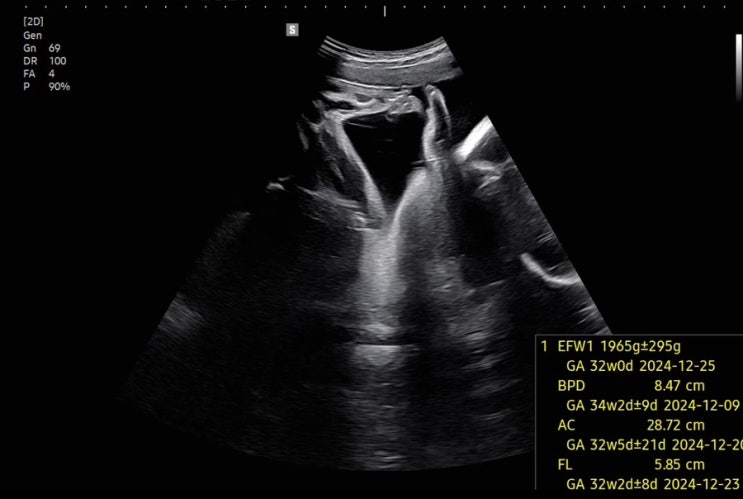

임신 34주차 / 무난한 일상

11/18 오늘도 어김없이 힘차게 임산부 요가를 가봅니다 11/20 갑자기 먹고싶어진 마라탕과 꿔바로우 입맛이...